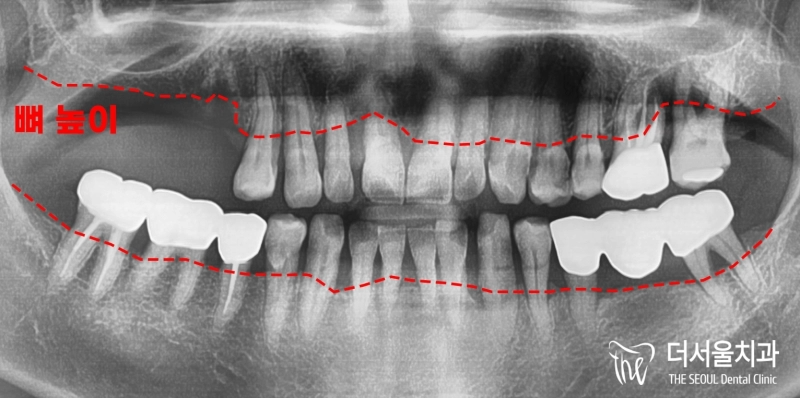

반갑습니다. 잠실 더서울 치과 박현성 원장입니다. 예전에 내원을 하셨던 환자 중에 따님분께 추천을 받아 오게 되었으며, 임플란트 수술을 받았던